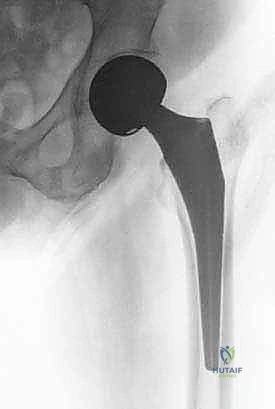

* الأشعة السينية (X-rays): هي المعيار الذهبي للتشخيص. يتم أخذ صورتين على الأقل (أمامية خلفية AP، وجانبية Lateral) لمفصل الورك والحوض بأكمله. تُظهر هذه الصور بوضوح مكان الكسر، ودرجة إزاحة العظام (التبدل).

رأب نصف مفصل الورك هو إجراء جراحي دقيق يتم فيه إزالة رأس وعنق عظمة الفخذ المكسورين والتالفين، واستبدالهما بمفصل صناعي معدني متطور.

لأنه يتم استبدال جزء واحد فقط من المفصل (وهو رأس الفخذ الكروي)، بينما يتم الاحتفاظ بتجويف الحُق الطبيعي (Socket) الخاص بالمريض كما هو دون تغييره. هذا يختلف عن "تغيير مفصل الورك الكامل" (Total Hip Replacement) الذي يتم فيه تغيير الرأس والتجويف معاً (والذي يُفضل عادة للشباب أو لمن يعانون من خشونة متقدمة في تجويف الحوض).